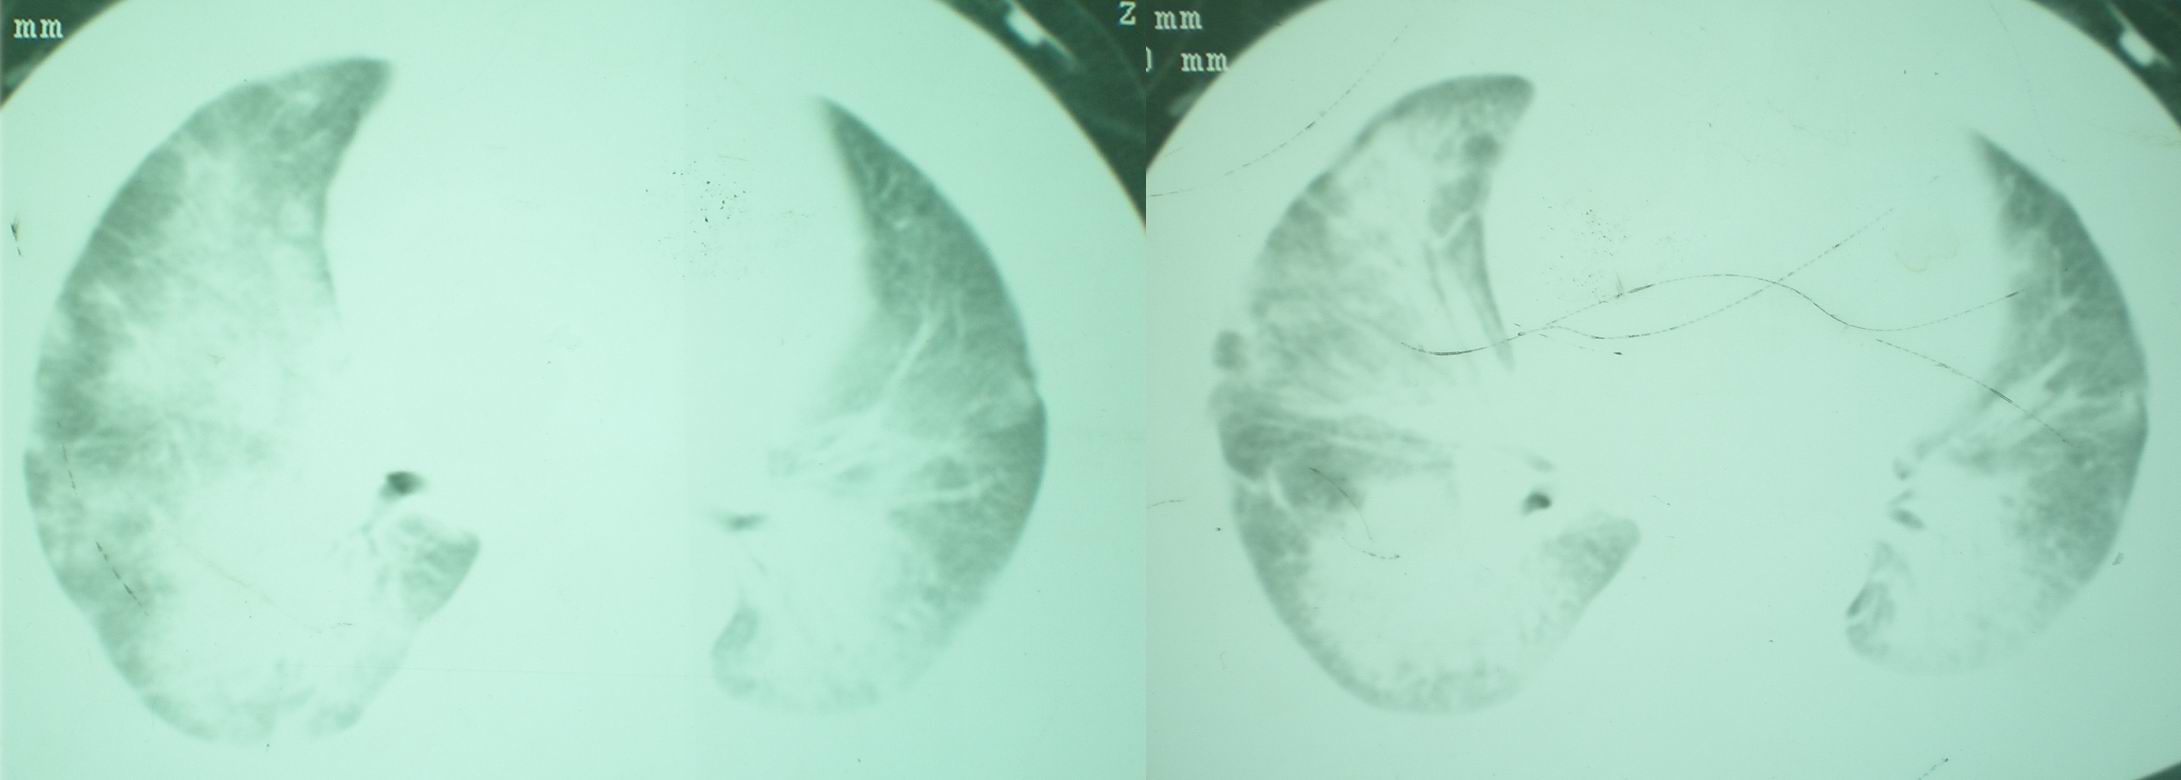

2008年11月18日今天的ct片

2008年9月18日ct片

2008年9月8日ct片:

[face=宋体]显然上级医院进行了抗结核,抗真菌,抗炎等治疗,目前病人肺内病灶基本消失,双侧胸腔积液,右侧积液量有吸收,抗结核一个多月,现在病人疑问,结核的诊断是否有疑义,抗结核是否继续,因为那个毕竟副作用大。[/face]

我仔细看了下病人的出院小结,当时情况危急,诊断里有1型呼衰。心包周围的是脂肪密度。结合三次ct扫描的图象分析,个人认为:1、病人目前肺部病灶基本消失,双侧胸腔内少量积液,抗结核治疗才一个多月,就算是结核,抗结核治疗有效果,为何效果如此好,一点纤维灶的痕迹都没有呢,再就是患者做过气管镜检查及活检、痰检均未找到结核的证据。所以不支持结核的诊断。

2、结合现在的ct片,考虑:肺水肿及真菌感染,双侧胸腔积液。